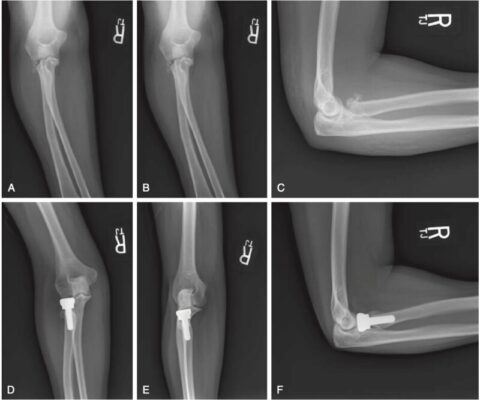

Đối với những trường hợp gãy xương cần điều trị bằng phẫu thuật, phương pháp điều trị sẽ phụ thuộc vào mức độ tổn thương. Điều trị phẫu thuật bao gồm cố định bên trong bằng nẹp vít với mổ hở, cắt bỏ chỏm quay hoặc thay thế đầu quay bằng thiết bị chỏm nhân tạo. Cắt bỏ chỏm quay mà không thay thế là một lựa chọn khi dây chằng bên và màng gian cốt còn tốt, mặc dù các nghiên cứu về kết quả lâu dài cho thấy những kết quả thành công trái ngược nhau (Tejwani 2007). Đối với những người trẻ tuổi, việc lựa chọn cố định bằng vít hay thay thế phụ thuộc vào mức độ gãy nát.

Trong các trường hợp gãy xương quay đơn độc không liên quan đến chấn thương dây chằng ở khuỷu tay, phương pháp phẫu thuật sẽ nhằm duy trì độ vững của mô mềm của khuỷu tay. Tập luyện sau phẫu thuật thường gồm các bài tập tầm vận động chủ động và chủ động có trợ giúp. Các bài tập thụ động không được khuyến khích. Không chịu trọng lượng trong 6 – 8 tuần cho đến khi đạt được sự liền xương và chỉ nên bắt đầu với sự đồng ý của bác sĩ phẫu thuật. Dây thần kinh gian cốt sau (posterior interosseous nerve, PIN) có thể bị tổn thương hoặc bị căng trong khi phẫu thuật và cần thông báo cho bác sĩ phẫu thuật nếu có triệu chứng tổn thương dây thần kinh này. Nếu có tổn thương dây chằng phối hợp, quy trình tập PHCN cần thay đổi phù hợp.